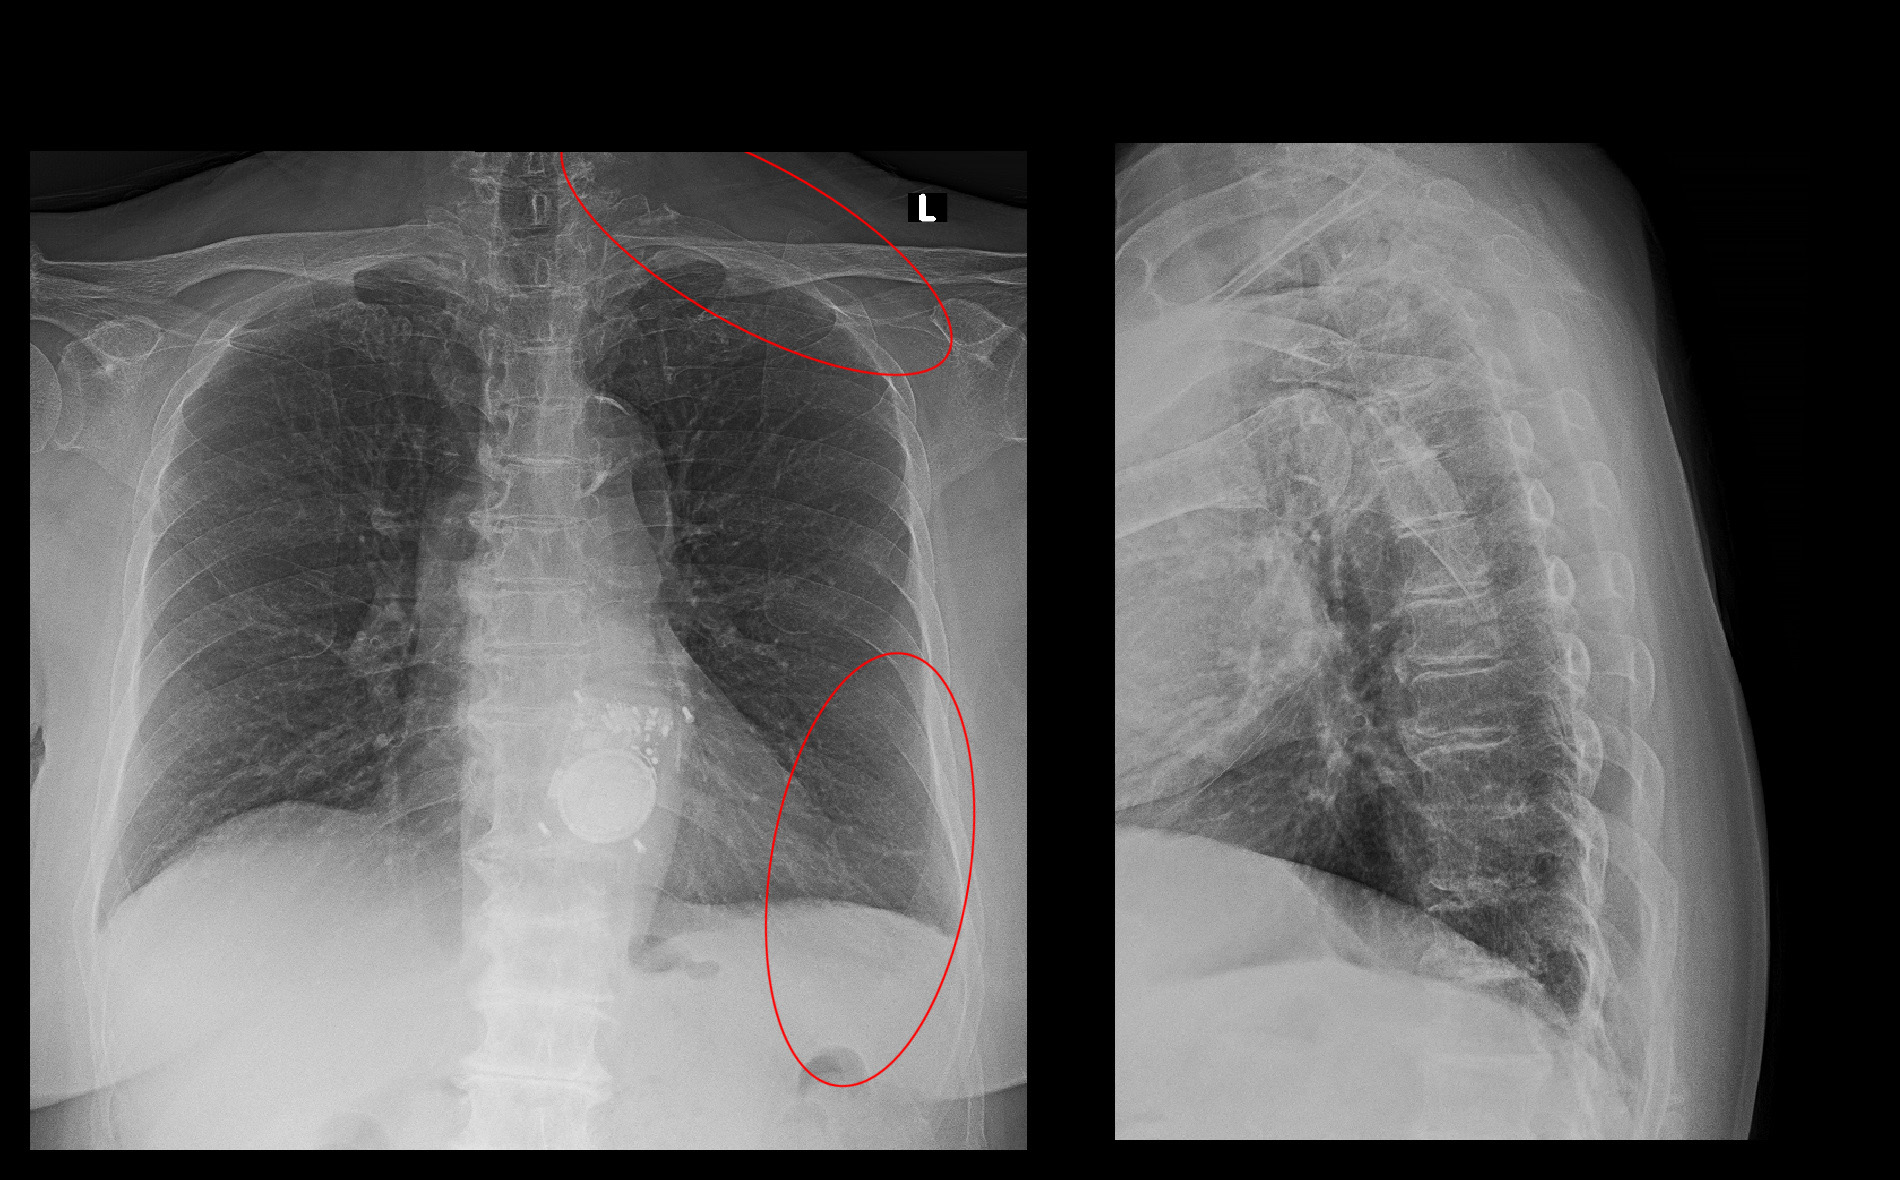

初診時Xp.jpg

初診時の胸椎のレントゲン像ですが、患者さんの訴えは心臓近傍痛の他にも左頚部痛もあるため、患者さんの症状は頚椎に起因する可能性も考慮されるものでした。

胸椎MRI検査では、胸椎左側に高輝度領域が確認されますが、軽度の胸水と判断され、水平断では明確な左右差もないため、心臓近傍痛の原因ではないと判断しました。